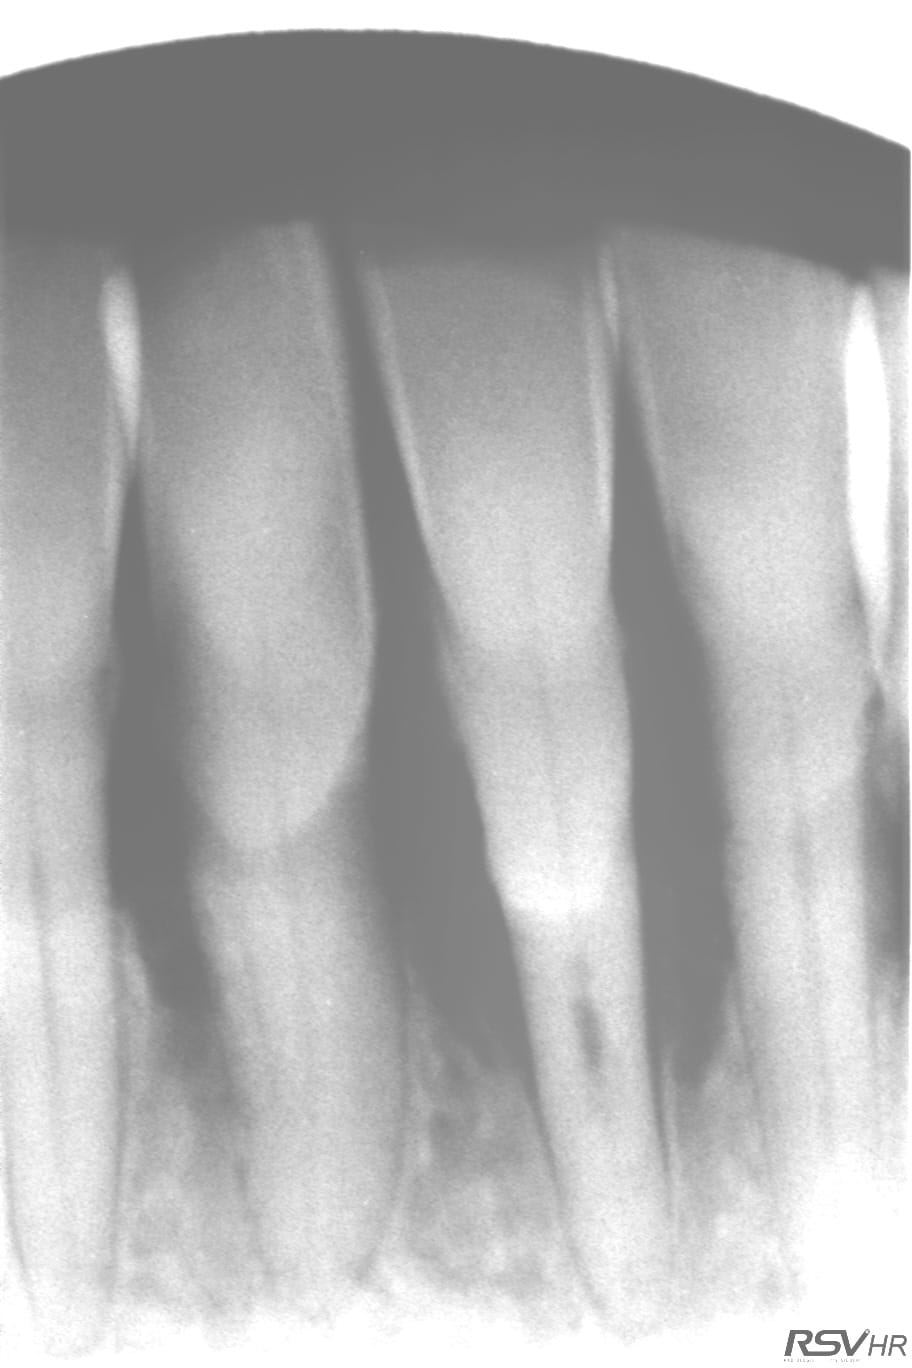

tu aurais une radio des dents restantes ?

voici le cliché

Ok, on a encore un rapport couronne/racine de 1/1 environ. Même si la 42...